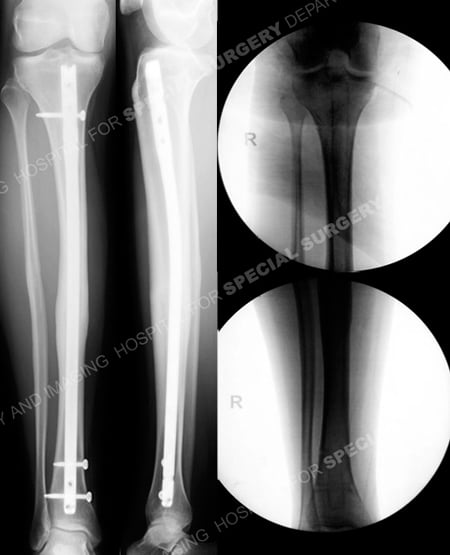

Anteroposterior and lateral radiographs 6 months following surgery (left images) illustrating a healed tibial malunion in acceptable alignment. Intraoperative fluoroscopic images (right images) following removal of hardware at 12 months.